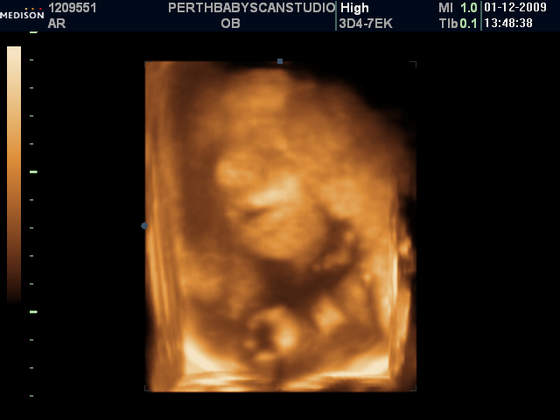

W naszym miescie na polnocy szkocji, o ile nie ma zadnych komplikacji, robia programowo tylko jedno usg (w 13 tygodniu):-(. My bardzo chcielismy znac plec dziecka dlatego pojechalismy do innego miasta (2 godziny drogi) i zaplacilismy £75 za usg ktore mialo byc w 2d ale mila pani doktor zrobila nam prezent na swieta i dostalismy tez zdjatka w 3d (ktore normalnie kosztuja £130) . Teraz przynajmniej wiemy ze bedziemy mieli sliczna i zdrowa coreczke:-) A to nasza Maja

Taka Misia - Pysia Moja:-)